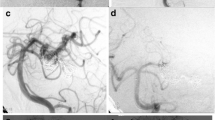

A–C Conventional axial MDCT,MRI images showing vascular lesion at the left crural cistern, with surrounding vasogenic edema. D, E AP, oblique, DSA projections, demonstrating dissecting aneurysm at the left P2 segment with underfilling distal to the aneurysm. F, G AP,LAT, DSA after aneurysmal packing and parent artery occlusion. H, I Six-month follow-up angiogram with partial refilling of the aneurysmal sac through the leptomeningeal collaterals. J, K Follow-up, MRI (showing regression of the aneurysm size and the surrounding edema)

Three months after aneurysm packing and PAO, minimal aneurysm recurrence was observed in one patient. The aneurysm has been packed by coils. Five months later, the patient complained of the headache. The follow-up angiogram showed minimal refilling of the distal part of the aneurysm by retrograde filling through leptomeningeal collaterals supplying the branches of the occluded artery (Fig. 6).